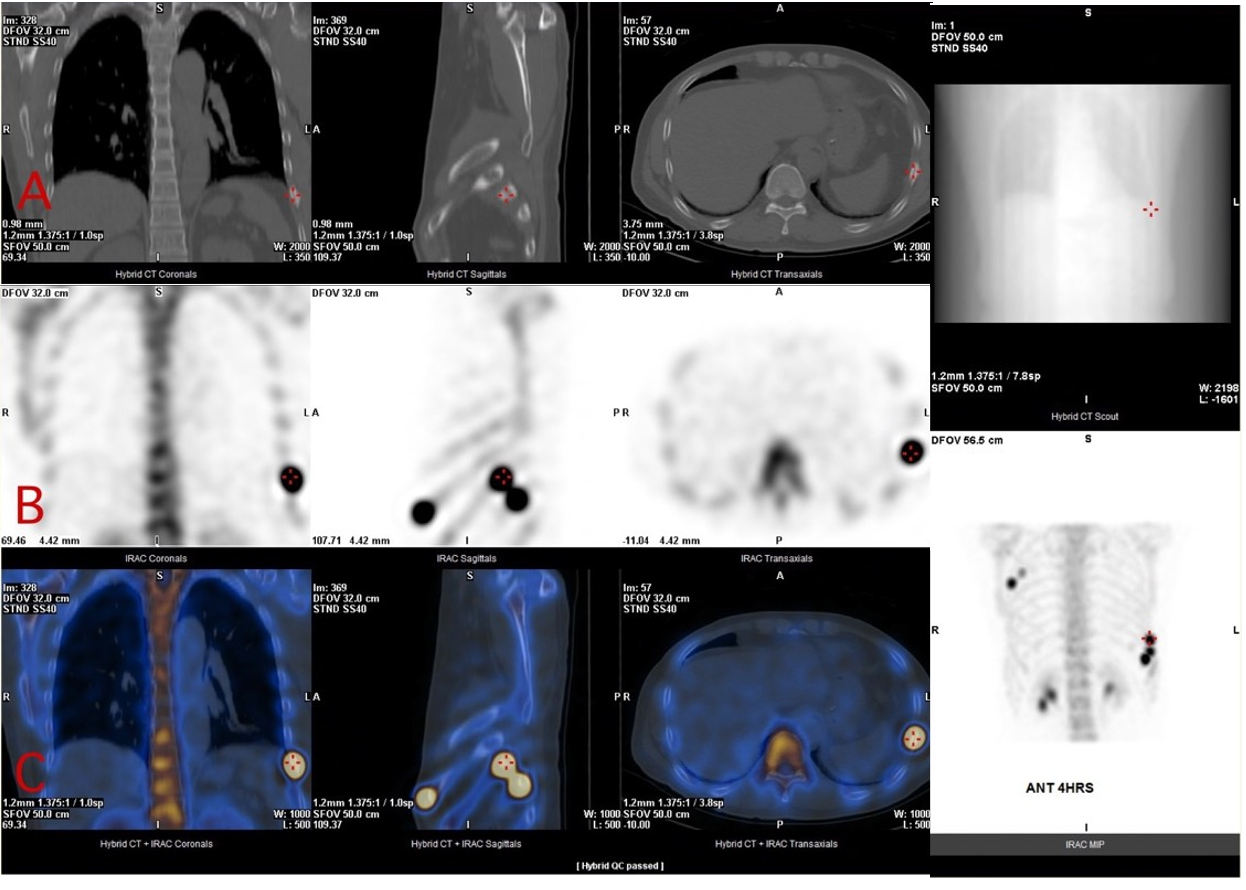

Figure 2 Nuclear scintigraphy with hybrid image of the patient’s rib cage. (A) CT scan of the lesioned rib. (B) Bone scan image with obvious lesioned rib in black. (C) SPECT image of the right 3rd lesioned rib with a red cross on it.

Figure 3 Nuclear scintigraphy with hybrid image of the patient’s rib cage. (A) CT scan of the lesioned rib. (B) Bone scan image with obvious lesioned rib in black. (C) SPECT image of the right 4th lesioned rib with a red cross on it.

Figure 4 Nuclear scintigraphy with hybrid image of the patient’s rib cage. (A) CT scan of the lesioned rib. (B) Bone scan image with obvious lesioned rib in black. (C) SPECT image of the left 8th lesioned rib with a red cross on it.

Figure 5 Nuclear scintigraphy with hybrid image of the patient’s rib cage. (A) CT scan of the lesioned rib. (B)Bone scan image with obvious lesioned rib in black. (C) SPECT image of the left 9th lesioned rib with a red cross on it.

Figure 6 Nuclear scintigraphy with hybrid image of the patient’s rib cage. (A) CT scan of the lesioned rib. (B) Bone scan image with obvious lesioned rib in black. (C) SPECT image of the left 10th lesioned rib with a red cross on it.